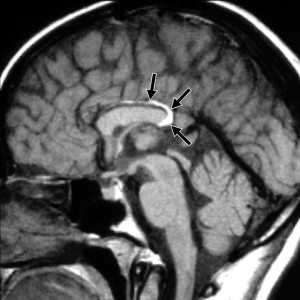

а) Определение:

• Увеличивающийся в размерах перелом костей свода черепа в смежных с посттравматической энцефаломаляцией отделах

1. Общие характеристики лептоменингеальной кисты:

• Лучший диагностический критерий:

о Стабильная или расширяющаяся линия перелома свода черепа после травмы головы

• Локализация:

о Наиболее часто - теменная кость

2. Рекомендации по визуализации:

• Совет по протоколу исследования:

о Рутинная бесконтрастная КТ в режиме исследования головного мозга и костей

3. Рентгенологические признаки:

• Рентгенография:

о Линейное литическое поражение черепа с фестончатыми краями

4. КТ признаки лептоменингеальной кисты:

• Бесконтрастная КТ:

о В острую стадию мозговая ткань и спинномозговая жидкость (СМЖ) выходят между краями костного дефекта

о Последующее развитие энцефаломаляции в смежных с переломом отделах

5. МРТ признаки лептоменингеальной кисты:

• Т1-ВИ:

о Киста изоинтенсивна по отношению к СМЖ, сообщается с субарахноидальным пространством

• Т2-ВИ:

о Те же изменения, что и на Т1 -ВИ